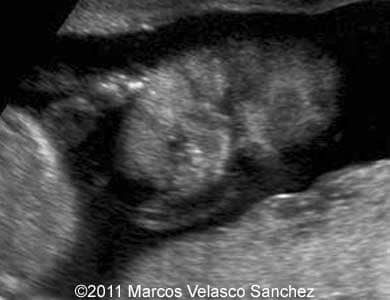

This is a case of a bilateral cleft lip associated with the cleft palate. A 25-year-old G2 P1 was referred to our department at 21 weeks of gestations. She had non-contributive personal or family history. We discovered bilateral cleft lip and palate. There were no other associated malformations.

Images 1- 4: Image 1; 21 weeks, Images 2-4; 24 weeks. Bilateral cleft lip and palate.